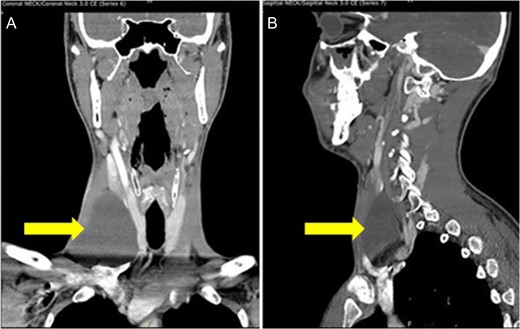

Our patient was a 29-year-old Caucasian male who presented to the clinic with a non-painful right sided anterior neck mass. Aspiration of the mass yielded 20 ml of straw colored fluid and resulted in a reduction of the mass’s size. Cytology of the fluid was negative for any malignant cells, and confirmed to be normal lymphatic fluid. The patient was seen 10 days later when the mass returned to its previous size. Computer tomography (CT) scan of the neck revealed an ovoid cystic appearing lesion deep to the sternocleidomastoid muscle, adjacent to the carotid artery. It measured ~7.6 cm in length by 6.8 cm in transverse dimensions and by 3.9 cm in AP dimensions. No associated lymphadenopathy was noted. However, the internal jugular vein was medially displaced (Fig. 1).

CT scan of the neck shows an ovoid cystic appearing lesion present at the base of the right neck (A: Coronal view and B: sagittal view).